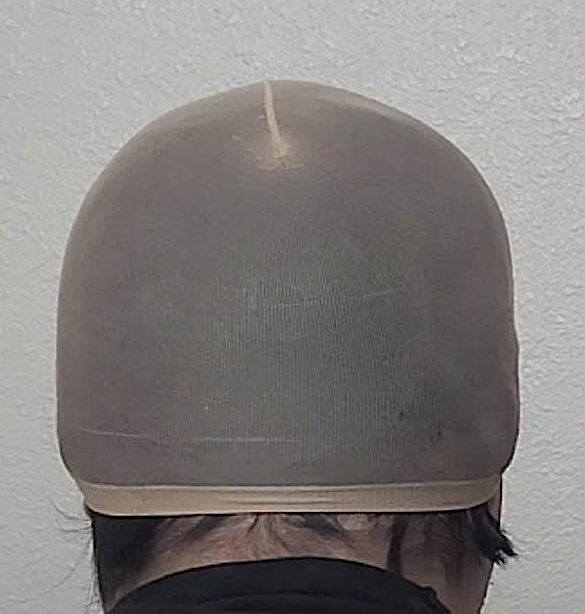

Patient 51

Desire for taller and rounder head shape.

Two stage custom skull implant augmentation technique.

Desire for taller and rounder head shape.

Two stage custom skull implant augmentation technique.